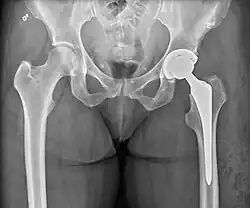

Post-operative projectional radiography is routinely performed to ensure proper configuration of hip prostheses.

The direction of the acetabular cup influences the range of motion of the leg, and also affects the risk of dislocation.[16] For this purpose, the acetabular inclination and the acetabular anteversion are measurements of cup angulation in the coronal plane and the sagittal plane, respectively.

Center of rotation: The horizontal center of rotation is calculated as the distance between the acetabular teardrop and the center of the head (or caput) of the prosthesis and/or the native femoral head on the contralateral side.[95] The vertical center of rotation instead uses the transischial line for reference.[95] The parameter should be equal on both sides.[95]